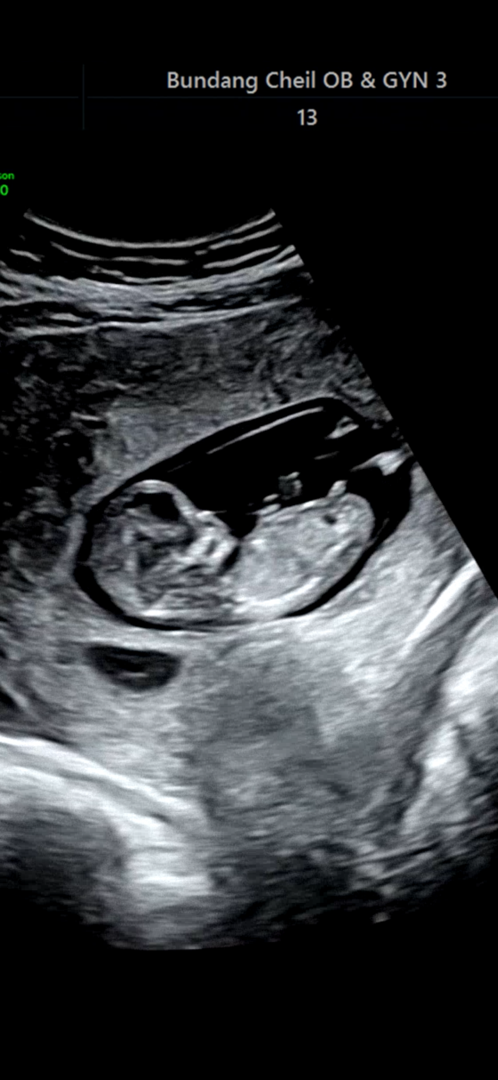

11주5일 각도법 도와주세요~~

1차 기형아검사 때 사진인데요. 아직 확인하기에는 이른건 알지만 저게 생식기 맞죠? 탯줄이나 이런게 보인건 아니겠죠? 각도법으로 보면 딸 같은데 딸일까요? 아직 이를까요?

영상이나 다른사진있으면 좋을거같아용 ㅎㅎ 딱 저 사진 한장으로만 봐선 아들같은데 반전으로 딸일수도있죠ㅎㅎ!!